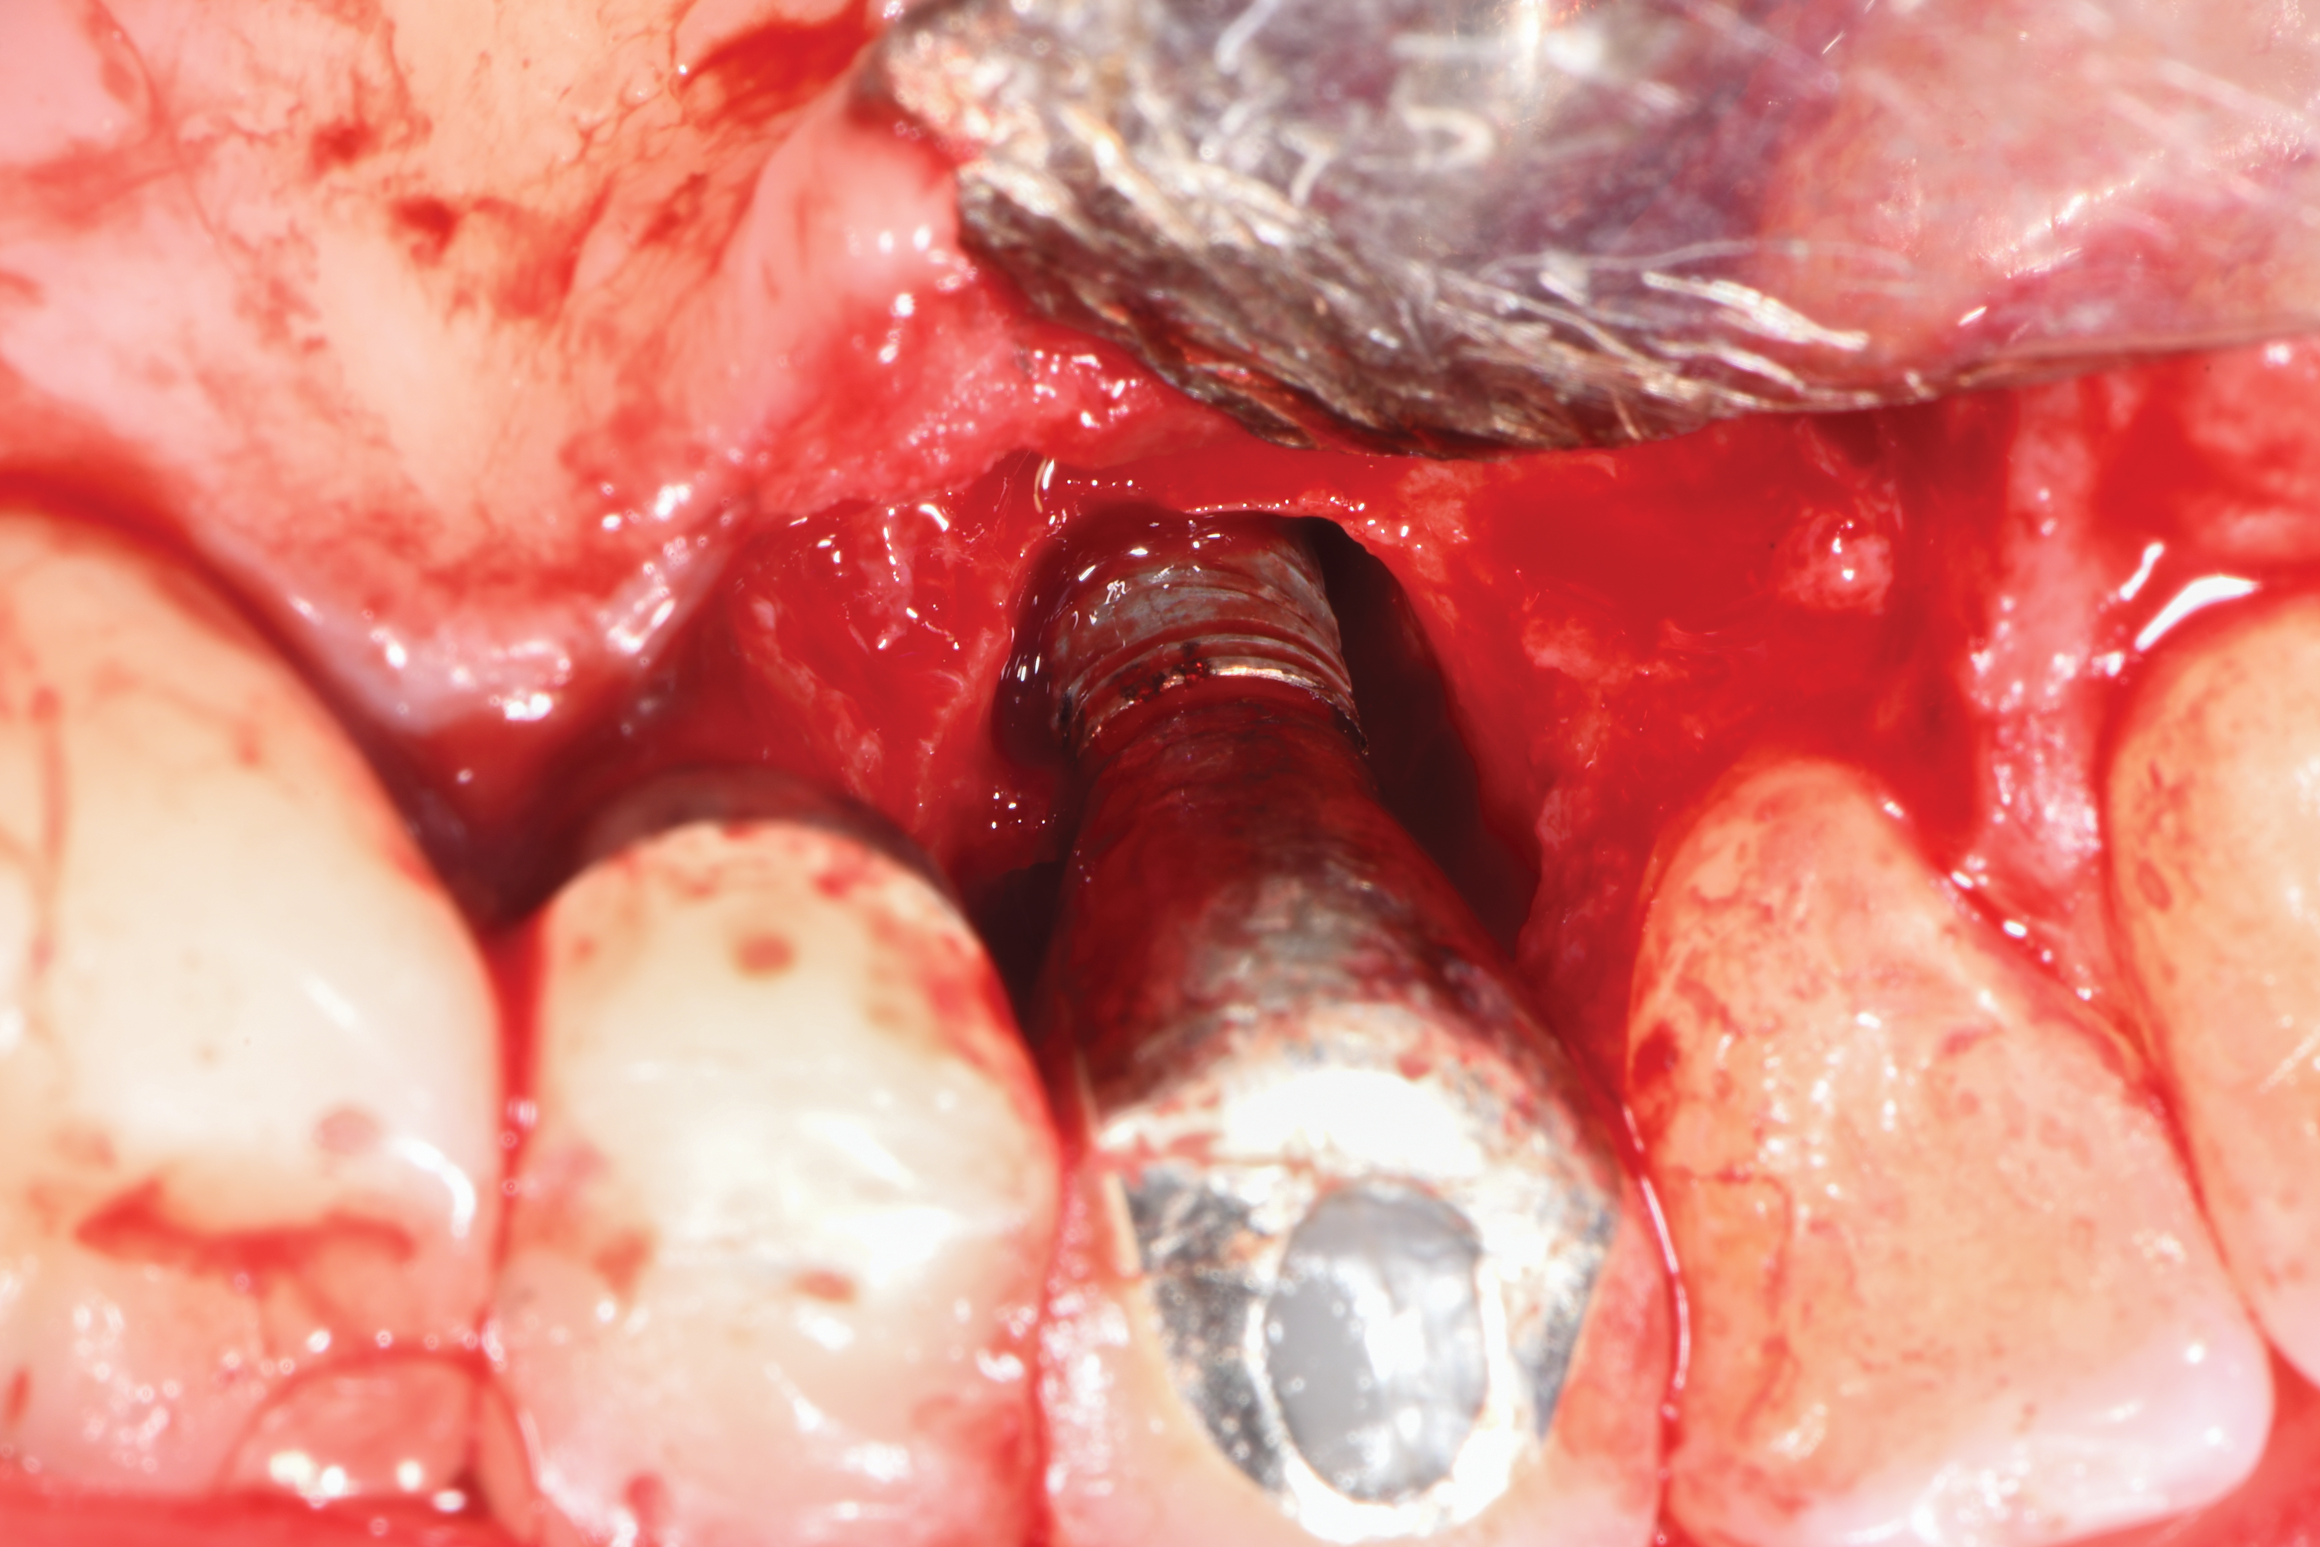

After local anesthesia was administered, full-thickness flaps were elevated from the buccal and lingual aspects of tooth No. 27 to the distobuccal and lingual aspects of tooth No. 31. Removal of granulomatous tissue from the implant site allowed visualization of a combination lesion with two walls at the distal and two to three walls at the mesial with a circumferential configuration on the lingual (Figure 12). The surface was initially treated with a 50% solution of citric acid for 30 seconds, which was burnished on with cotton pellets followed by thorough rinsing with sterile saline. This was followed by implantoplasty using 12-fluted followed by 30-fluted surgical-length finishing burs that provided access to the base of the defect. Because the crown was cemented, which obviated access, a matte-like surface could not be achieved; thus, the goal was to reduce the threads and remove the outer affected surface to expose fresh titanium (Figure 13). At this stage, the implant was wiped again with citric acid and rinsed with sterile saline.

Fig 13. Implantoplasty was completed. Some bleeding at the distal obscured one thread that was impossible to plasty. The surface was subsequently wiped with citric acid prior to grafting.

Figure 13

The two cases presented demonstrate the success that can be achieved using implantoplasty to decontaminate the entire dental implant surface. How this approach differs from past endeavors is that the surface modification used in these cases extended to the depth of the patients' infrabony lesions in an effort to achieve reosseointegration. Several case report articles in the literature with human histologic evidence show that regeneration may be an achievable endpoint for implants compromised by peri-implantitis.26-28 While these three case reports utilized different surface management protocols in humans, what they had in common is that the superstructure/crown was removed to attain access for cleaning all aspects of the surface.26-28 Removal of the superstructure/crown, however, is not always possible as some crowns are cemented, and if removed they will require replacement. The benefit of the longer 30-mm length burs in the bur kit used in the present cases is that they allow for better access due to a variety of shapes, reaching even to the subcrestal portions of the defect, which can be obviated by crowns that cannot be removed.29 While this may not prohibit achieving a completely matte-type finish on the implant surface, the fact that the threads and outermost portion get reduced/eliminated would facilitate decontamination.

Peri-implantitis destruction results in bony defects with a wide variety of morphologies.17 Many of these lesions contain an infrabony component with multiple walls, which would suggest that a regenerative approach be considered as a part of the treatment. Chan and colleagues performed a systematic review and meta-analysis of various surgical approaches for peri-implantitis, including access flap and debridement, surgical resection, application of bone grafting materials, and guided bone regeneration.34 Within the limitation of their systematic review, the authors concluded that application of grafting materials and barrier membranes resulted in greater probing depth reduction and radiographic bone fill. However, they noted that there was a lack of high-quality comparative studies to support this statement. Implantoplasty may be used to achieve a surface absent bacterial contamination in both the supra- and subcrestal components of a peri-implantitis defect and, thus, provide a uniform way to address the entire implant surface. This enables the surgeon to utilize a regenerative approach for the subcrestal area, even in the narrowest of defects, while not forcing the use of resective treatment, which can leave the implant body more exposed to the oral environment. The finishing burs used in the present cases are effective at eliminating/reducing the implant threads and creating a more matte-like implant surface that is not overly smooth, which is desirable because a highly polished endpoint is less suitable for bone-to-implant contact.25,35,36 Removal of the implant crown provides optimal access for thread removal and surface smoothing (Figure 19) and allows for healing within a closed environment.35-37 Use of burs with longer surgical length and myriad shapes provides enhanced access to all aspects of the implant body than what was typically available in the past. Moreover, the use of both 12- and 30-fluted burs is beneficial considering that implants made from grade 5 titanium may require a lesser fluting to aid in reducing the outer surface of the implant, while the 30-fluted burs can help to avoid excessive reduction of narrower-diameter implants, such as seen in Case 1.